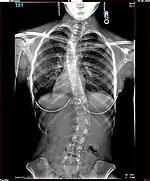

Polio patients would sometimes develop scoliosis, a condition where the spine becomes curved laterally (from side to side).[5] Harrington realised that existing treatments for scoliosis, which relied heavily on physical therapy, were inappropriate for patients paralysed by polio, and began to research new treatments. An early method he tried for scoliotic polio patients was manual correction of the scoliotic deformity at the time of surgery, and internal fixation of each facet. There were some benefits to this treatment but Harrington found that the fixation would not hold.[4] The hooks and threaded rods used would corrode and break, causing curvature to return to the spine. Two patients of this procedure died.[5]

The Harrington Rod, or Harrington implant, is a device for the straightening of the spine inside the body, designed by Paul Harrington. The device consists of a stainless steel rod, attached to the spine at the top and bottom of the curve with hooks. Attached ratchets are then tightened to distract or straighten the spine. Following surgery to insert the rod, the patient wears a postoperative plaster cast or brace for a few months, until vertebral fusion has occurred, after which the cast or brace is removed.[5]

The major drawback of the Harrington Rod is that it straightens out the normal front to back curvature of the segment of the spine that is fused, which in many patients results in a flat back deformity, also known as "flatback syndrome". Advances in surgical techniques and technology in the late 1990s were eventually able, in most cases, to correct scoliosis without causing flatback syndrome, leading to the gradual phasing out of the Harrington Rod.[6]